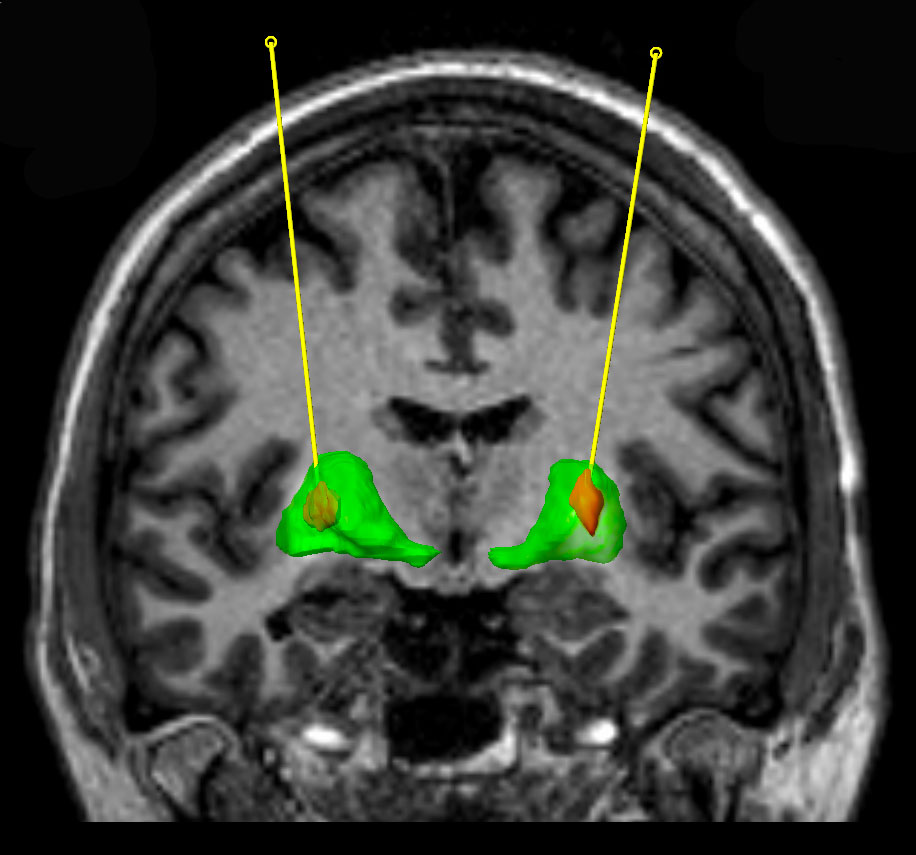

This initial failure gave rise to another clinical study at the Frenchay Hospital in Bristol (UK) in which GDNF was released inside the brain, in an area called the striatum. Tiny plastic tubes were implanted in the brain allowing for the GDNF to be pumped in.

GDNF was pumped into the striatum (green area). Source: Bankiewicz lab